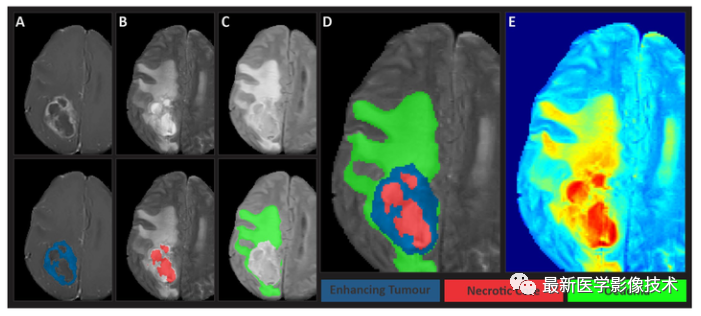

该数据集包括 60 例标注训练样本、15 例未标注验证样本,以及 30 例测试样本。每例提供四种序列 MR 的输入图像(t1w, t1c, t2w, t2f)以及胶质瘤的分割结果,标注内容主要包括非增强肿瘤核心(NC)、水肿(Oedema)和增强型肿瘤(ET):增强肿瘤:包括对比后图像上相对于对比前图像而言 T1 信号显着增加的肿瘤的所有部分。这包括任何离散可见的硬脑膜尾部,但不包括邻近的血管,即使异常增大。内在 T1 高信号也不包含在该标签中。非增强肿瘤核心:包括肿瘤核心的所有不增强的部分(即通常会被外科医生切除的部分)。这包括坏死、囊性变、钙化,甚至延伸至肿瘤的外生性骨质增生。这还包括固有的 T1 高信号,例如瘤内出血和脂肪。周围非增强 FLAIR 高信号:是肿瘤周围 FLAIR 信号异常的整个范围,不属于肿瘤核心的一部分。

左图是金标准结果,右图是网络预测结果。